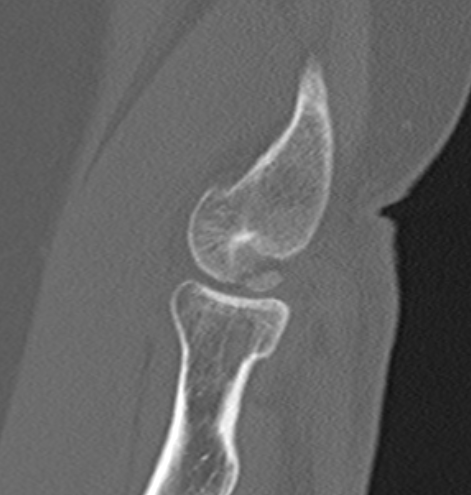

CT

MRI